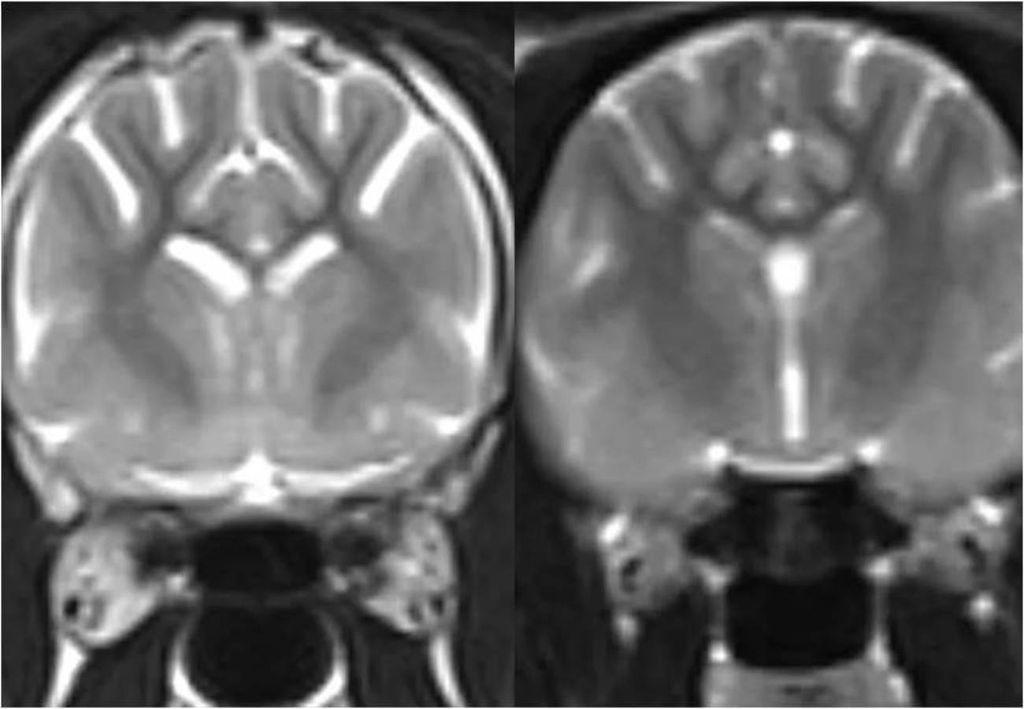

Pesquisadores da Universidade de Edimburgo, na Escócia, examinaram o cérebro de 25 gatos de diferentes idades após sua morte, incluindo os animais que tinham sinais de demência em vida, como confusão, distúrbios do sono e aumento da vocalização.

Eles analisaram imagens microscópicas dos cérebros para estudar o acúmulo de beta-amiloide nas sinapses (as conexões das células cerebrais), uma proteína tóxica e uma das características que definem a doença de Alzheimer.

Foi observado então que os gatos, assim como os humanos, também possuem um acúmulo de beta-amiloide nas sinapses. Além disso, os pesquisadores também encontraram evidências de que astrócitos e microglia — tipos de células de suporte no cérebro — "comeram" as sinapses afetadas. Este processo é importante durante o desenvolvimento do cérebro, mas pode contribuir para a perda de sinapses na demência.